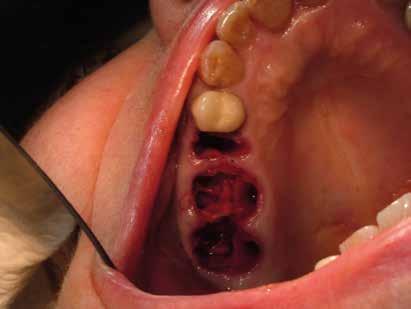

Alla visita di rivalutazione è emerso un ulteriore peggioramento della situazione, confermata anche dall’esame radiografico, con parodontopatia, sanguinamento al sondaggio, infiammazione diffusa, alitosi, difetto parodontale verticale mesiale a 2.3, residui radicolari 1.4, 1.6, 1.7, 3.6, 3.8 e carie destruenti di 1.5, 2.6, 3.5, 3.7 (con lesione endoperio) e 4.7 con estrusione e carie (Figg. 1, 2)

La proposta che il paziente ha accettato è stata poi quella, previa bonifica di tutti gli elementi irrecuperabili, di riabilitare con impianti prima il 1° e 4° quadrante e in seguito il 2° e 3° e procedere poi alla protesi definitiva in un’unica soluzione.

Al controllo ematologico è emersa una emoglobina glicosilata molto superiore la percentuale accettabile a procedere (il valore era 9,3%) e deficit di D-25OH che è stato risolto con una terapia di ripristino con colecalciferolo 25000 U.I. Data la stretta correlazione tra emoglobina glicata e affezioni orali, è ormai routine seguire un percorso che porta alla bonifica della bocca e contestualmente, che aiuta il paziente anche con il controllo della glicemia. In prima battuta comunque, abbiamo sottoposto il paziente a una seduta orale. Per via del suo stato di salute (abbiamo stabilito per lui un rischio alto) durante ogni seduta invasiva abbiamo sempre monitorato il paziente con rilevazioni multiple dei parametri e reperendo un accesso venoso pe-

riferico. Si è eseguito la maggior parte delle estrazioni in un’unica seduta operatoria, a esclusione degli elementi 2.6 e 4.7 che sono stati mantenuti perché presentavano mobilità ma non segni di focolai infettivi attivi e che si è deciso di estrarre in un secondo momento. Il follow-up post estrattivo ha consentito anche di valutare la risposta tissutale e la guarigione degli alveoli. Non è stata sospesa la terapia con l’acido acetilsalicilico. Il PRGF è stato importante per evitare alveoliti che avrebbero rallentato la guarigione (Figg. 4-6).

L’esame CBCT ha rivelato un quantitativo di osseo sufficiente a procedere con l’intervento implantare, anche se erano ancora visibili le zone delle estrazioni; inoltre ha evidenziato una lesione osteolitica a carico del 3.5 che abbiamo dunque deciso di estrarre (Figg. 7-20).